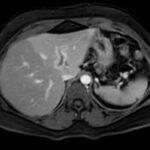

En este caso, presentamos una paciente femenina de 43 años de edad con antecedente de uso de ACO, a quien se le diagnosticó Trombosis portal mediante TC de abdomen c/cte. EV y trombofilia con mutación en el factor II de protrombina 20210, con evolución favorable.

Paciente femenina de 43 años, antecedente de obesidad grado I. Medicación habitual uso de ACO. Antecedente quirúrgico: una cesárea. Presenta cuadro clínico caracterizado por epigastralgia súbita de moderada intensidad. Se automedica con Buscapina sin mejoría del cuadro, por lo que acude a guardia. Le realizan TC y la derivan con diagnóstico de trombosis portal de la rama izquierda.

Se solicita nueva tomografía para descartar progresión de la trombosis y se vuelve a instaurar analgesia y anticoagulación EV.

Hallazgos imagenológicos